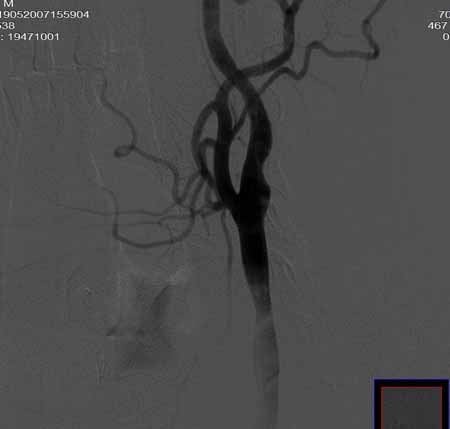

男,60岁。

腹主动脉、颈总动脉、颈内动脉狭窄支架置入术,最少放了三个支架吧,得十几万吧。

颈总动脉支架置入术。

指针宽了些

wallstent9*50可以全部覆盖,可以节约些

当然楼住的选择无可指责